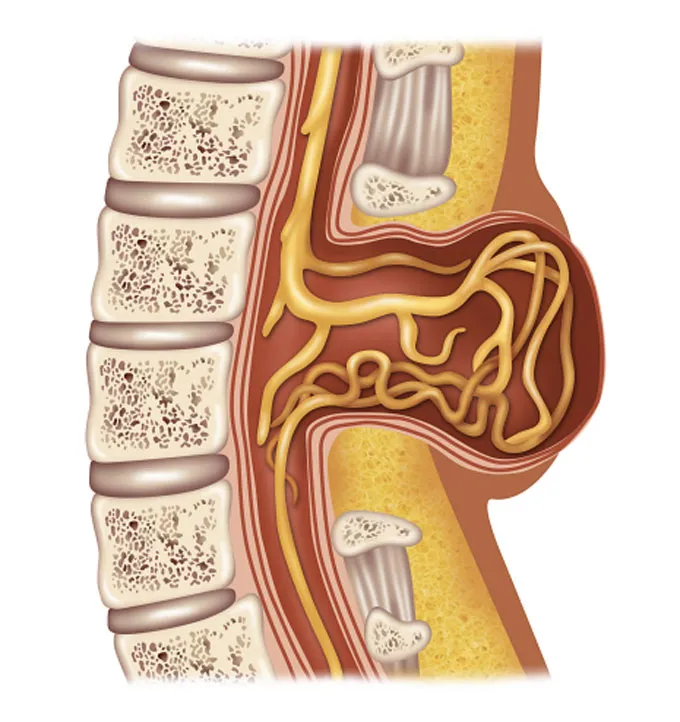

Proper spine development in a fetus (shown here) isn’t guaranteed. In spina bifida, the spine and spinal cord don’t form correctly, which can result in disabilities. A new kind of fetal surgery attempts to repair the defect and damage done in the womb.

The new technique attempts to heal nerve damage caused by spina bifida, a disabling birth defect. In this condition, the bony tissue of a fetus’s spine doesn’t knit together properly around the spinal cord. That can cause a kaleidoscope of medical issues, including lifelong paralysis and bladder and bowel problems.

In the United States, roughly 1 in every 2,800 babies are born with spina bifida. This abnormality leaves the delicate spinal cord exposed in the womb. Without the bony protection of the vertebrae, the spinal cord can bulge through the back, making it especially vulnerable to injury. Like a chemical that burns, amniotic fluid washing over the open spinal cord can degrade it. And as the baby grows, it rubs against the walls of the uterus, damaging unprotected nerve cells.

Beyond paralysis and other serious problems, this damage can cause fluid to build up in the brain. Some babies require a shunt surgically implanted in the days or weeks after birth for drainage. That can be lifesaving, but it’s also lifelong — a permanent implant that can malfunction or spur infection.